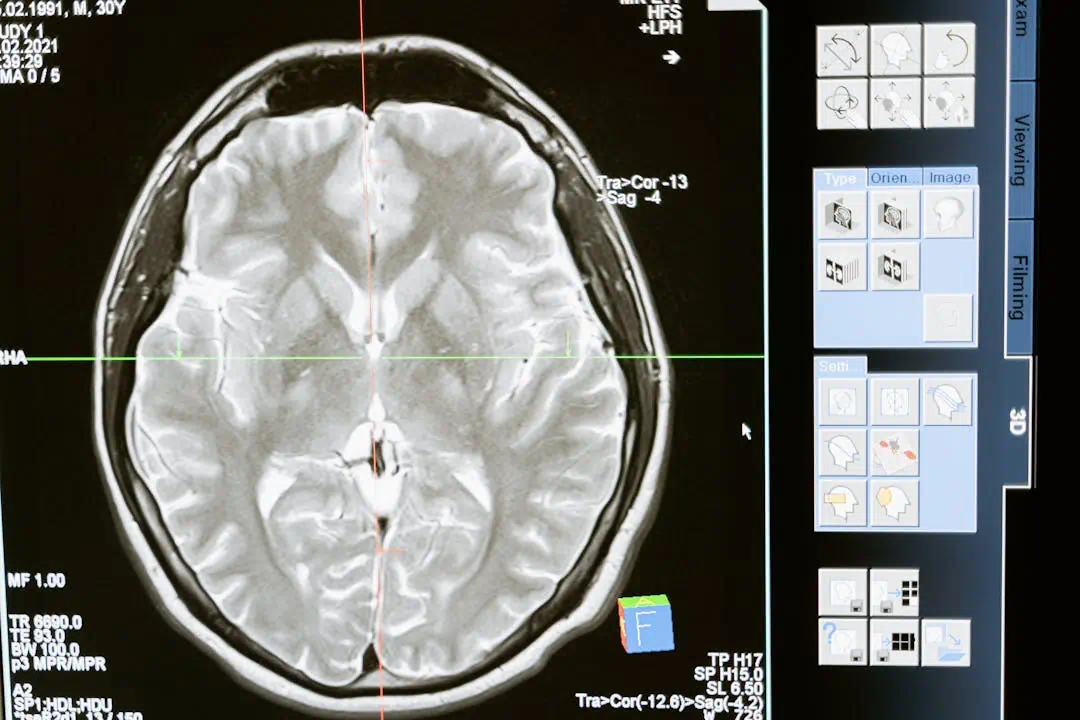

갑작스러운 신체 이상으로 병원을 찾았을 때, 의사로부터 뇌경색이라는 진단을 받는다면 당황스러움보다 먼저 치명적인 위험성을 인지해야 합니다. 뇌경색은 쉽게 말해, 뇌로 가는 혈액 공급이 차단되어 뇌 조직이 죽어가는 현상입니다.

🔵 뇌경색은 뇌졸중의 한 종류로, 전체 뇌졸중의 약 80%를 차지할 만큼 발병 비율이 매우 높습니다.

뇌세포가 산소와 영양분을 받지 못해 5분 이내 괴사 시작

❗ 뇌는 한 번 손상되면 회복이 극히 어렵기 때문에 뇌경색 초기증상을 빠르게 포착하고 대응하는 것이 무엇보다 중요합니다.

단 4시간 30분 안에 치료를 시작해야 생존율·회복률 급격히 상승하며, 6시간 이상 지연 시 뇌 손상은 불가역적으로 진행됩니다.